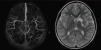

El tratamiento al alta fue con ácido acetilsalicílico 75mg/día y rehabilitación física, su puntaje en la escala modificada de Rankin (EMR) fue de 4. Cuatro meses después se efectuó una nueva ARM en la cual persistieron las alteraciones previamente observadas (fig. 2). Un año después del evento, la EMR es de 1, sin recurrencia de episodios isquémicos.

Estudio vascular por angioresonancia magnética realizado 4 meses después del egreso hospitalario, muestra persistencia del defecto de llenado identificado inicialmente en el segmento M1 izquierdo con circulación distal normal. A la derecha, secuencia T2 por resonancia magnética, muestra imagen hiperintensa consistente con zona de malacia localizada en la cabeza del núcleo caudado y porción medial del núcleo lenticular, la cápsula interna aparece integra.